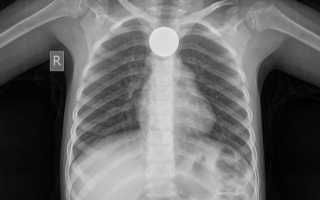

Инородное тело пищевода у детей в 80% случаев приходится на младший возраст, особенно до двух лет. Монеты составляют 80% от всех проглоченных инородных тел.

- Рентгенография грудной клетки и шеи необходима всем пациентам с подозрением на попадание постороннего предмета (для его локализации, вне зависимости от симптомов). Инородные тела в пищеводе располагаются во фронтальной плоскости, а в трахее – в сагиттальной плоскости.

- Для обнаружения проглоченных металлических предметов, особенно монет, может использоваться металлодетектор.